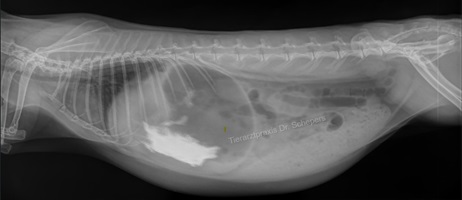

Röntgendiagnostik

Die sichere Diagnose wird durch ein Röntgenaufnahmen gestellt; hierdurch kann die Konsistenz des Mageninhalts (fest, flüssig, aufgegast) auch von weniger geübten Tierärzten sicher und objektiv beurteilt werden. Zudem besteht eine objektive Vergleichsmöglichkeit für spätere Verlaufskontrollen.

Die genaue Diagnose ist elementar für die anschließende Therapie:

• leerer Magen-Darm-Trakt, geschwächte Magen-Darm-Motorik, leichte Verstopfung => Zwangsfütterung notwendig

• Verschluss (mechanischer Ileus) oder massiv überfüllter Magen => Zwangsfütterung fatal!

Weiterhin kann objektiv beurteilt werden, wie groß der Magen tatsächlich ist, wie lange der Zustand bereits besteht (beim mechanischen Ileus v. a. anhand der Konsistenz des Mageninhaltes: anfangs homogen, anschließend "spiegeleiartig" durch beginnende Gasbildung) sowie inwieweit eine Magentympanie (= Aufgasung) beteiligt ist. Ein gewöhnlicher Kaninchenmagen ist rund, mit homogenem, strukturiertem Inhalt gefüllt und ragt maximal zu einem Drittel über den Rippenbogen hinaus.

Auch kann die Füllung des Magen-Darm-Trakts bereits einen deutlichen Hinweis auf einen Darmverschluss liefern: Bei dem typischen, im vorderen Dünndarmbereich lokalisierten Verschluss ist die Darmschlinge unmittelbar hinter dem Magenausgang leer und luftgefüllt, der dahinter befindliche Darm hingegen noch futtergefüllt.

Sitzt der Verschluss in einem anderen Darmabschnitt, kann der Darm zu größeren Anteilen mit Luft gefüllt sein oder gefüllte, stark dilatierte (= überdehnte) Areale aufweisen. In letzterem Fall kann der Magen (noch) eine normale Größe besitzen, da sich der Futterbrei zunächst im Dünndarm und erst später bis in den Magen zurückstaut.

Angeschoppte Köttel im Enddarm deuten auf eine dort befindliche Verstopfung hin.